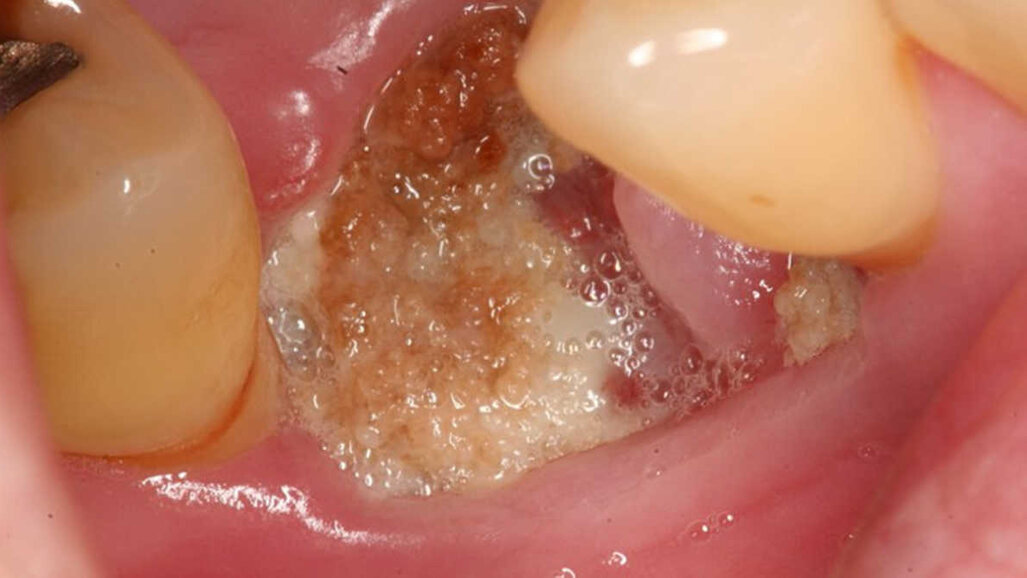

85-годишна жена, страдаща от остеопороза, се оплаквала от болка около имплант, който й е бил поставен преди година. При прегледа учените са установили открита и некротизирала кост, оток, зачервяване и гной около импланта. Първоначално е приложено стандартното лечение при подобни случаи – промивки с хлорхексидин, антибиотици и аналгетици, но в продължение на три месеца не се наблюдава подобрение. След което за осем седмици са й поставяни инжекции с терипаратид – хормон, стимулиращ образуването на нова кост, като през цялото време се прави проследяване за странични ефекти. Изследвани са били първоначалните нива на С-телопептид (СТх) – индикатор на костното ремоделиране, и остеокалцин – протеин, участващ в костното образуване.

Клиницистите са установили редица подобрения по време на лечението, както и през 6-месечния период на проследяване. Видимо некротизиралата кост изчезнала, раната заздравяла, нивата на СТх се повишили от 121 pg/ml на 294 pg/ml, а нивата на остеокалцина се покачили от 12.8 ng/ml на 18.5 ng/ml, като всичко това е белег за образуване на нова кост.